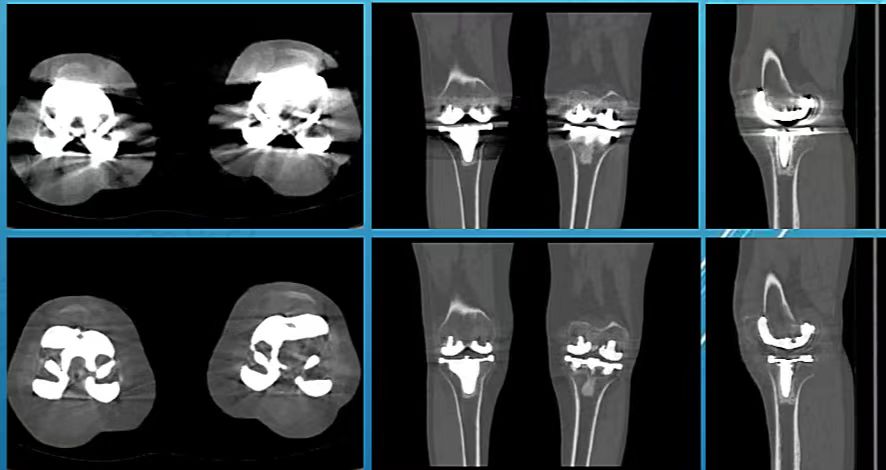

病例三:在四肢关节中应用

可以看到,在肘关节、髋关节、膝关节置换术中,应用单能重建图像伪影降低,金属植入物与周边组织关系清晰。